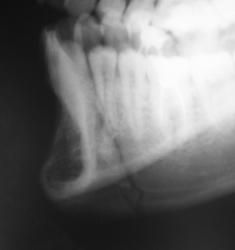

А это визави.

А у нас так ломают челюсти

Зашинировали

У этого 3 г. назад нелеченная травма, теперь остеомиелит